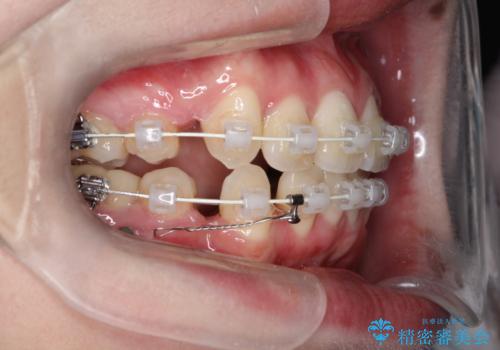

八重歯のワイヤーによる抜歯矯正 矯正治療と並行してセラミック治療も

- 八重歯と前歯のガタガタを主訴に来院されました。

左下の奥歯がすでに1本抜歯されており、ブリッジを装着されていました。

ブリッジを除去して、左下以外の上顎両側と右下の歯を合計3本抜歯して矯正する計画としました。